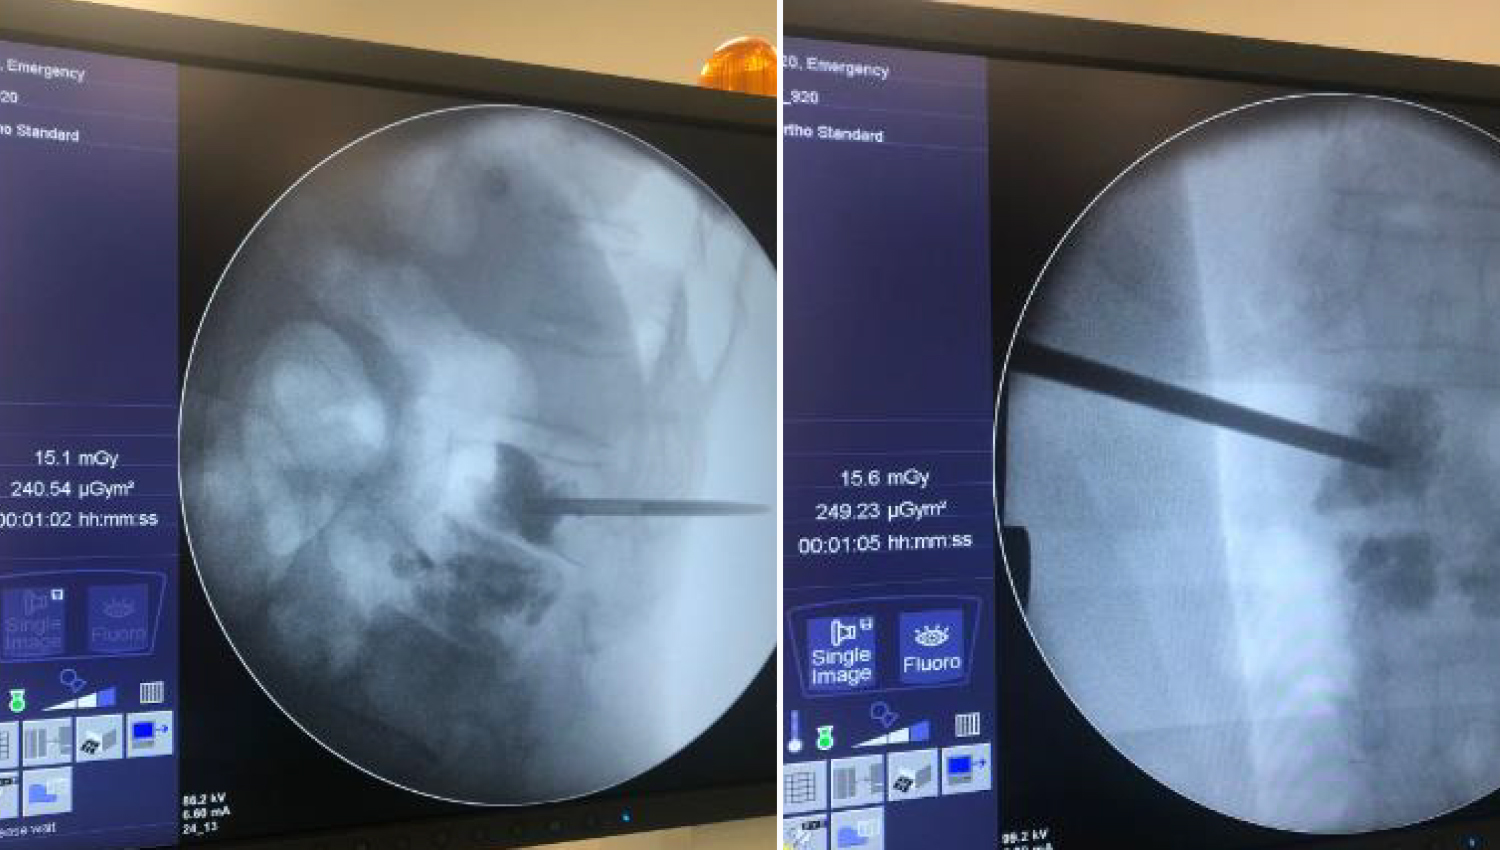

2.Imaging of the defect in the spine at the beginning of the operation.

4.Bone Filler and Pusher Cannulated Screw waiting in the prepared state are prepared to be applied to the defect area. With the application of Bone Cement, the change in imaging is observed.